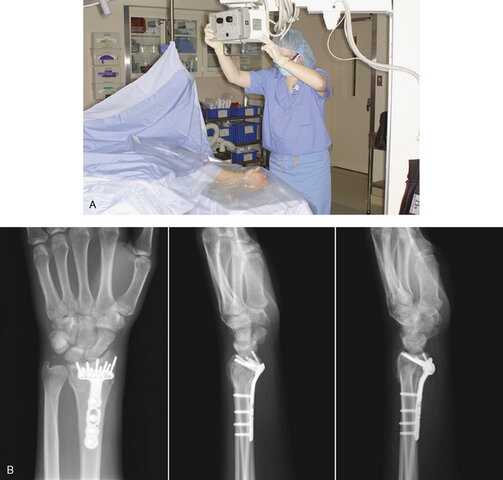

The discovery of x-rays was by William Conrad Röntgen in 1895. X-rays were discovered as Röntgen observed a fluorescent glow of crystals in his lab. The discovery of x-rays was by William Conrad Röntgen in 1895. X-rays were discovered as Röntgen observed a fluorescent glow of crystals in his lab.